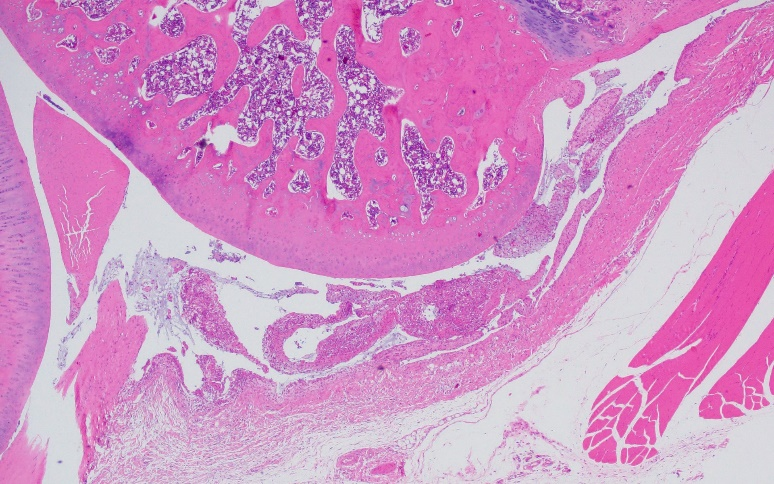

(2)組織病理學:給藥期結束,高劑量組動物給藥部位可見關節囊炎癥,停藥后有恢復趨勢。

高劑量組給藥部位:關節囊炎癥